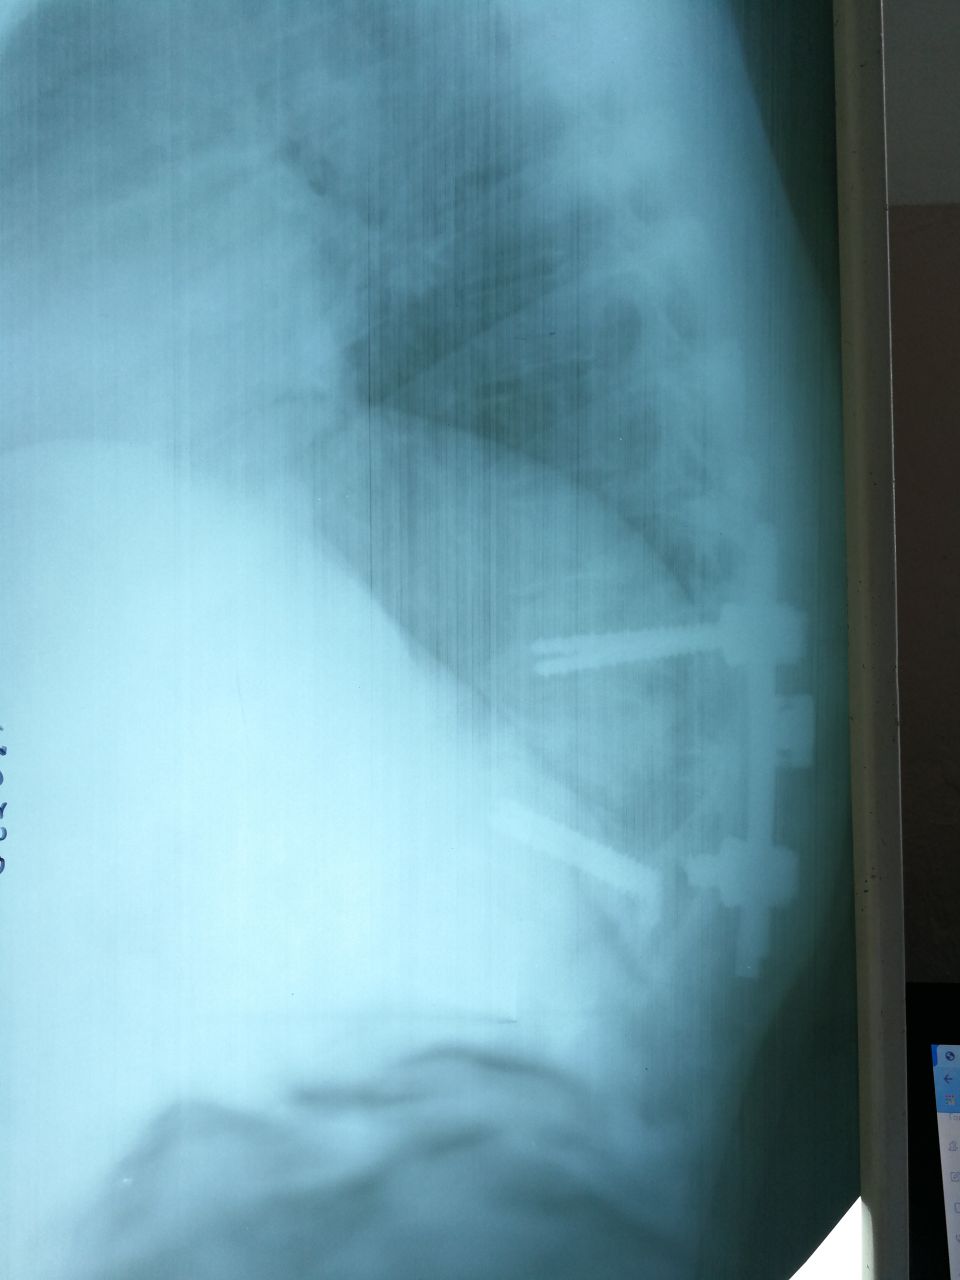

Определяются металлические тени винтов, введённых через ножки в тела позвонков, соединённые вертикальными штифтами.

Транспедикулярная фиксация позвонков

Перелом транспеда

С переломом 👍😁

Th12